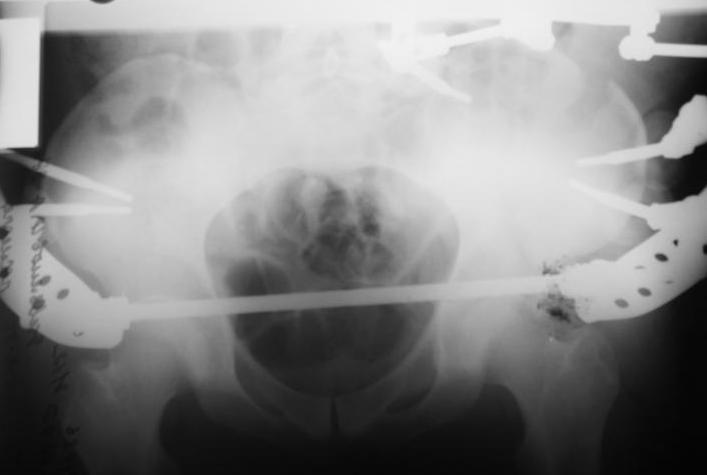

Поступил пациент после кататравмы (упал с высоты 4м). После обследования установлен Ds: Сочетанная травма. ЗТГК перелом 5-6 ребер справа. Ушиб левого леогкого. Оскольчатый перелом крыла подвздошной кости слева, со смещением. в экстренном порядке выполнена операция о/синтез таза стержневым аппаратом. Снимки прилагаются. Пациент со 2-го дня стал ходить без костылей. Из анамнеза жизни у пациента имеется гепатит В и С, с 1998г. употребляет наркотики (героин 1г в день нормальная доза). На контрольных снимках таза в аппарате смещение отломков сохраняется, да еще и стержни сломались. Подскажите ув.коллеги, как поступить в данной ситуации: оставить все как есть или добиваться репозиции в аппарате, или планировать на открытую репозицию. На сегодняшний день пациент стабилен, по анализам компенсирован. Принимает героин по другому справиться не может. С ув. Андрей

Уважаемый Андрей, у пациента имеется перелом передней колонны,и после наложения аппарата положение отломков ухудшилось. возможно не из-за ваших действий а за счет тяги четырехглавой мышцы. Обе ости настойчиво будут тянуть крыло вниз.